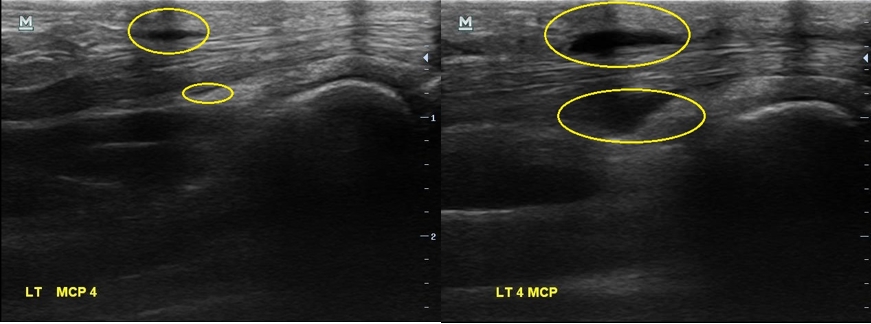

골프에 너무 빠져서 아파도 참고 치셨다는 분... 초음파 검사를 다시 해보니...

2주 전보다 힘줄에 염증이 훨씬 심해져 있었습니다. 그리고

이번에는 한 부위만이 아니라 손가락 굽힘 힘줄을 따라 전체적으로 염증이 퍼져있습니다.

나 : 2주만에 염증이 엄청나게 심해졌네요... 보이시죠?